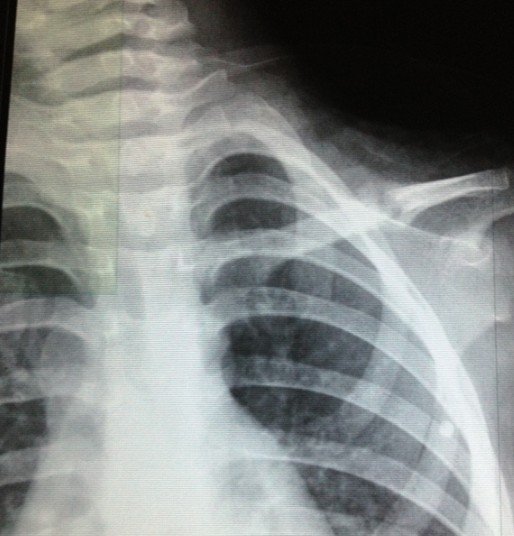

宝宝3岁半出车祸左锁骨骨折

2012.10.7日发送车祸,X片确诊为左锁骨骨折。现在已经自行把八字绷带取下,请问这样做可以吗?因为孩子的腋下已经开始有轻微溃烂的症状(掉干壳壳)前段时间因为出车祸导致孩子的左锁骨骨折,去医院打了八字绷带,刚好一个月去医院复查,医生说已经开始长骨痂,建议继续八字绷带半个月,今天宝宝一直吵着说腋下痛,我才发现宝宝的腋下有那种干裂的壳状的掉出,而且腋下非常的红。孩子的奶奶处于心痛孩子,就把绷带给取了,请问这样做妥当吗?会影响孩子骨折的生长吗?如可以取下,家长应该注意些什么细节呢?谢谢!“下面的X光片拍摄于2012年11月3日”